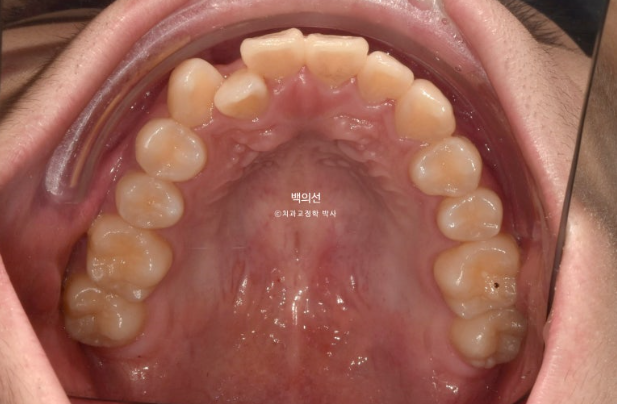

배열도 완벽 합니다.

지금도 충분히 좋지만 추가장치 제작에 들어갔고 25년 2월부터 25년 7월까지 추가장치를 다 낀 후 치료를 마무리 했습니다.

마찬가지로 14개 추가장치를 모두 챙겨가 해외에서 바꿔끼면서 치료를 진행했습니다.